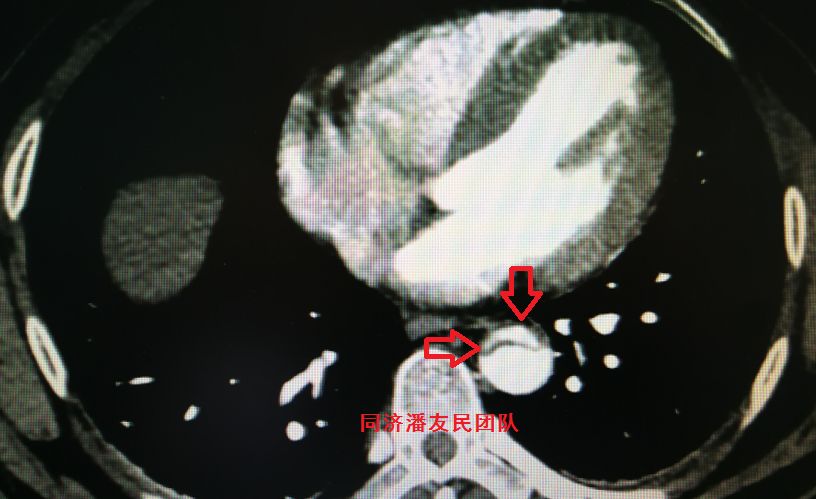

结果在上级医院复查胸腹主动脉CTA,在平扫CT提示主动脉夹层的对应层面,证实了主动脉夹层(图3~6)。同时发现升主动脉及主动脉弓均有夹层撕裂 (图7~8) 。 因此,正确诊断应该是 A型 (1型) 主动脉夹层。

图6:CTA显示图5相应层面,钙化点内移征及夹层撕裂内膜片(红箭头所示)